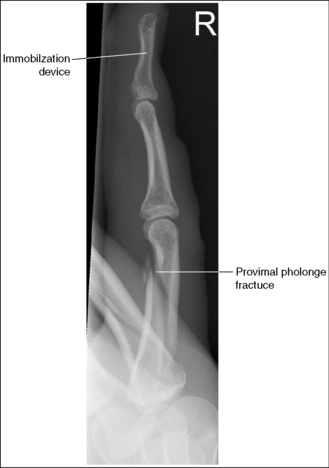

• Flex the unaffected fingers into a tight fist, allowing the finger of interest to remain extended. To visualize the proximal phalanx, it may be necessary to extend the affected finger with an immobilization device or to tape the unaffected fingers away from the affected finger. If the unaffected fingers are not drawn away from the proximal phalanx of the affected finger, they will be superimposed on the area, preventing adequate visualization (see Image 8). An immobilization device should not be used to extend the finger if a fracture is suspected and the device causes stress to the fractured area (see Image 9).

Image 8

Image 9